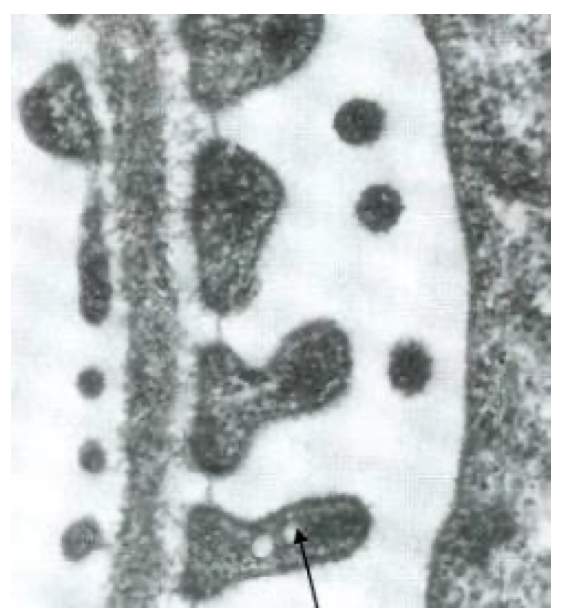

На электронномикроскопическом фото представлен фрагмент почечного фильтра. Что отмечено стрелкой?